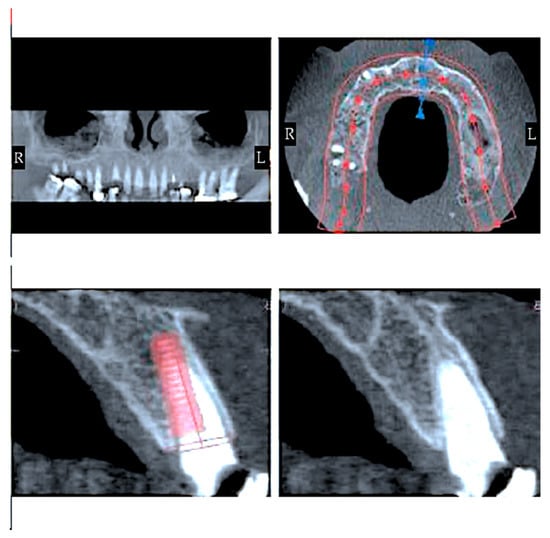

- Instrumental examinations (three-dimensional radiography, intraoral optical impression);

- Image matching and transformation from .dicom to .stl;

- Surgical intervention (Figure 5).